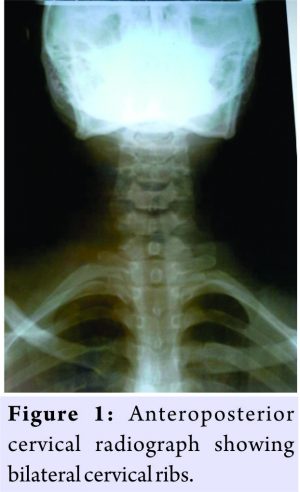

A 28-year-old female soldier was referred to the spine surgery unit with right shoulder pain of 3 years duration. Pain radiated into the hand and was worsened at night and by elevation of the right upper limb. She had episodes of paresthesia, loss of sensation to both fine and crude touch at C8 and T1 dermatomes, coldness, and swelling of the right upper limb. Right-hand interossei muscle power was 4/5 (MRC grading). Anteroposterior X-rays of the cervical spine (Fig. 1) showed bilateral cervical ribs which were longer on the right than on the left. Magnetic resonance imaging of the cervical spine showed short segment cervical cord syrinx formation at C2/C3 level and bilateral cervical rib with brachial plexus compression on the right side. Right cervical rib excision was done under general anesthesia through an anterior approach (an 8cm longitudinal incision just above the right clavicle) with the patient in supine position. Intraoperative findings were of a complete cervical rib. Platysmal repairs over a drain then subcuticularethylone 2.0 closure. There was complete resolution of all symptoms by the 5-month follow-up visit. 8 months after the initial operation, she re-presented at the outpatient department with similar symptoms on the left upper limb. She had excision of the left cervical rib which intraoperatively was noted to be an incomplete cervical rib with a fibrous cord tethering the brachial plexus. At 12-month follow-up visit, the patient had full resolution of all symptoms with the full use of both upper limbs.